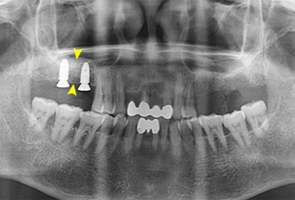

임플란트 시술에서 골이식은 매우 중요합니다. 골이식술은 치조골의 양과 질이 좋지 않을 때 자가골이나 동종골, 이종골 등을 이식하여 임플란트의 지지를 위한 골 재생을 도모하는 술식입니다. 치아가 상실된 지 오래되었거나 만성 치주염 등으로 치조골의 양과 질이 나빠지게 된 경우 골이식이 꼭 필요합니다.

CT검진을 통해 뼈이식에 필요한 뼈의 양과 수술방법을 결정하게 되는데 이때는 다양한 치료 경험을 가진 치료자의 능력 또한 중요합니다.

| 치아가 빠진 지 오래된 경우 | 임플란트 식립 시 심을 공간이 부족한 경우 |

| 치주질환으로 잇몸뼈에 손상이 있는 경우 | 심은 임플란트의 뿌리가 노출 되었을경우 |